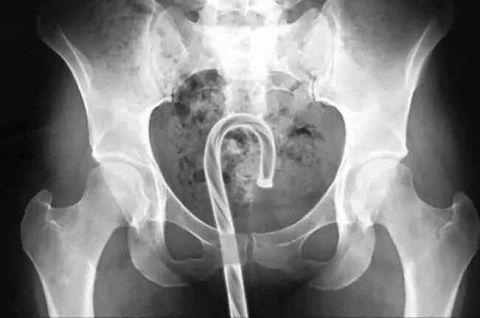

这玩意儿是自己插进去的